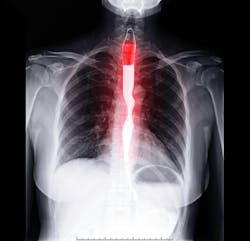

A novel test developed by Johns Hopkins Kimmel Cancer Center investigators could give gastroenterologists insight into which patients with Barrett’s esophagus are likely to progress to esophageal cancer or an abnormal collection of cells called high-grade dysplasia.

This information could help physicians determine how to monitor or manage patients during clinical care.

The test, called Esopredict, is a PCR (polymerase chain reaction)-based laboratory test that, from biopsy samples, measures the level of DNA methylation changes in the genes RUNX3, p16, HPP1 and FBN1. Methylation changes often occur early during abnormal cell growth, before conditions can be detected clinically. By combining these results with patients’ age, physicians can gauge the likelihood that patients’ premalignant conditions will advance and help them determine how often to monitor or manage patients with potential neoplastic progression.

Using the tool in previously collected biopsies from 240 patients with Barrett’s esophagus from six medical centers, researchers determined that the overall risk for neoplastic progression was 5.1%. Patients in the highest risk group had a 21.7% risk of developing high-grade dysplasia or esophageal cancer, compared with a 6.87% risk among those in the high moderate group, a 3.25% risk for those in the low moderate group and just 1.27% among those in the lowest risk group. A description of the work was published online August 14 in The American Journal of Gastroenterology. The test is now commercially available.

Researchers ran the Esopredict test on 209 biopsy samples previously collected from patients with Barrett’s esophagus at Johns Hopkins and Allegheny Health Network, Capital Digestive Health, Mayo Clinic, University of Maryland and University of Connecticut healthcare sites. The first 99 patient samples served as a training set in which a model algorithm was designed, and the next 110 patient samples were analyzed as a validation set in which the algorithm was tested. Samples also were assayed from an additional group of 31 patients who went on to develop high-grade dysplasia or esophageal cancer and who had follow-up intervals longer than five years.

Some 78 of the 209 patients progressed to having high-grade dysplasia or esophageal cancer within five years of biopsy collection, while the remaining 131 had no progression over the next five years. Investigators ran several calculations with Esopredict to try to predict the likelihood of cancer or high-grade dysplasia developing. They stratified patients into two main groups: lower risk (further refined into low and low-moderate risk categories) or higher risk (further refined into high moderate or high-risk levels) of progressing to more serious conditions. Overall, they found that patients in the two higher risk groups to be 6.4 times more likely to progress to high-grade dysplasia or esophageal cancer within five years. Compared with patients considered lowest risk, the highest risk patients were 15.2 times more likely to progress to these more serious conditions.